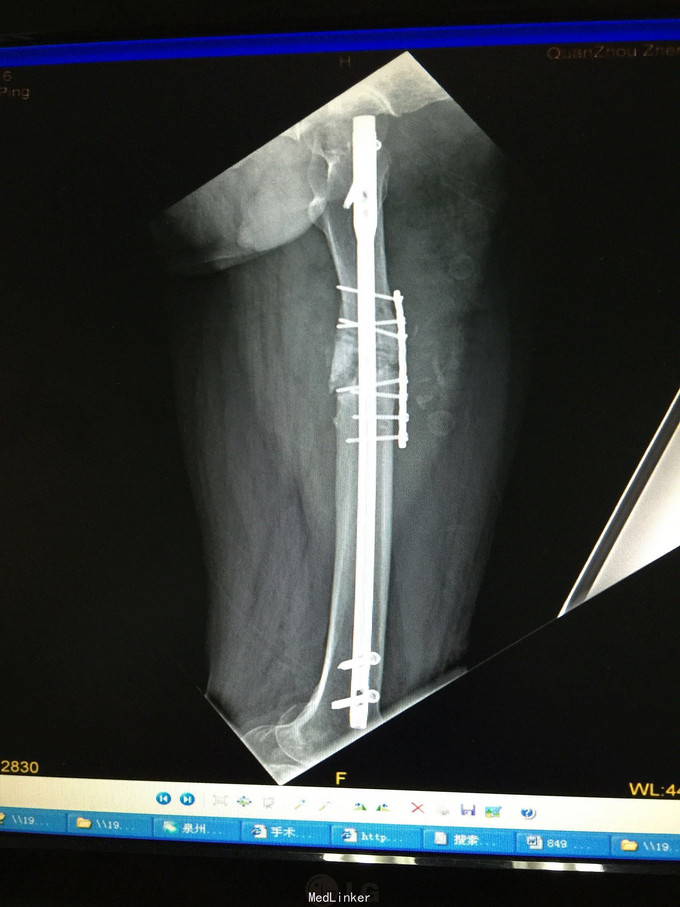

左股骨中上段骨折术后骨不连

主诉:左股骨骨折术后伴局部酸痛11个月

左大腿局部可见手术疤痕,骨折端处无切开疤痕,局部无压痛,无异常活动,关节活动正常。

诊断:左股骨中上段骨折术后骨不连 处理:左股骨骨折术后骨不连断端清理+防旋钢板内固定+取髂骨植骨术

术后半年 讨论 考虑股骨中上段骨折 应力集中 近段一枚螺钉稳定性不够?